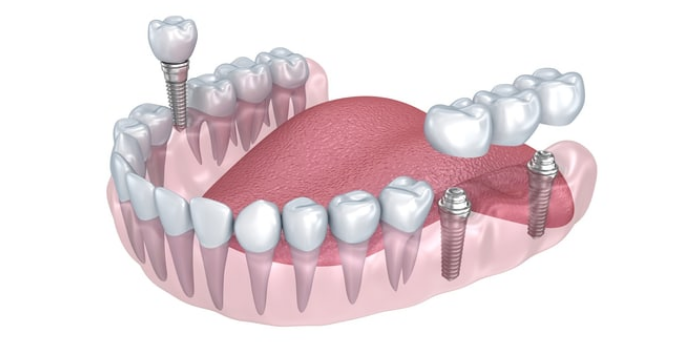

随着口腔医学的发展,更多缺牙者选择了种植牙。

相比活动假牙不舒服、难清洗、容易引起口腔黏膜病变,种植牙更稳固耐用,舒适美观,咀嚼功能好,一次种植,终生受用。

暨大穗华口腔集诊疗、教学和科研为一体的口腔专业机构。目前在广州开设多家机构。院内设立专门的数字化种植中心。